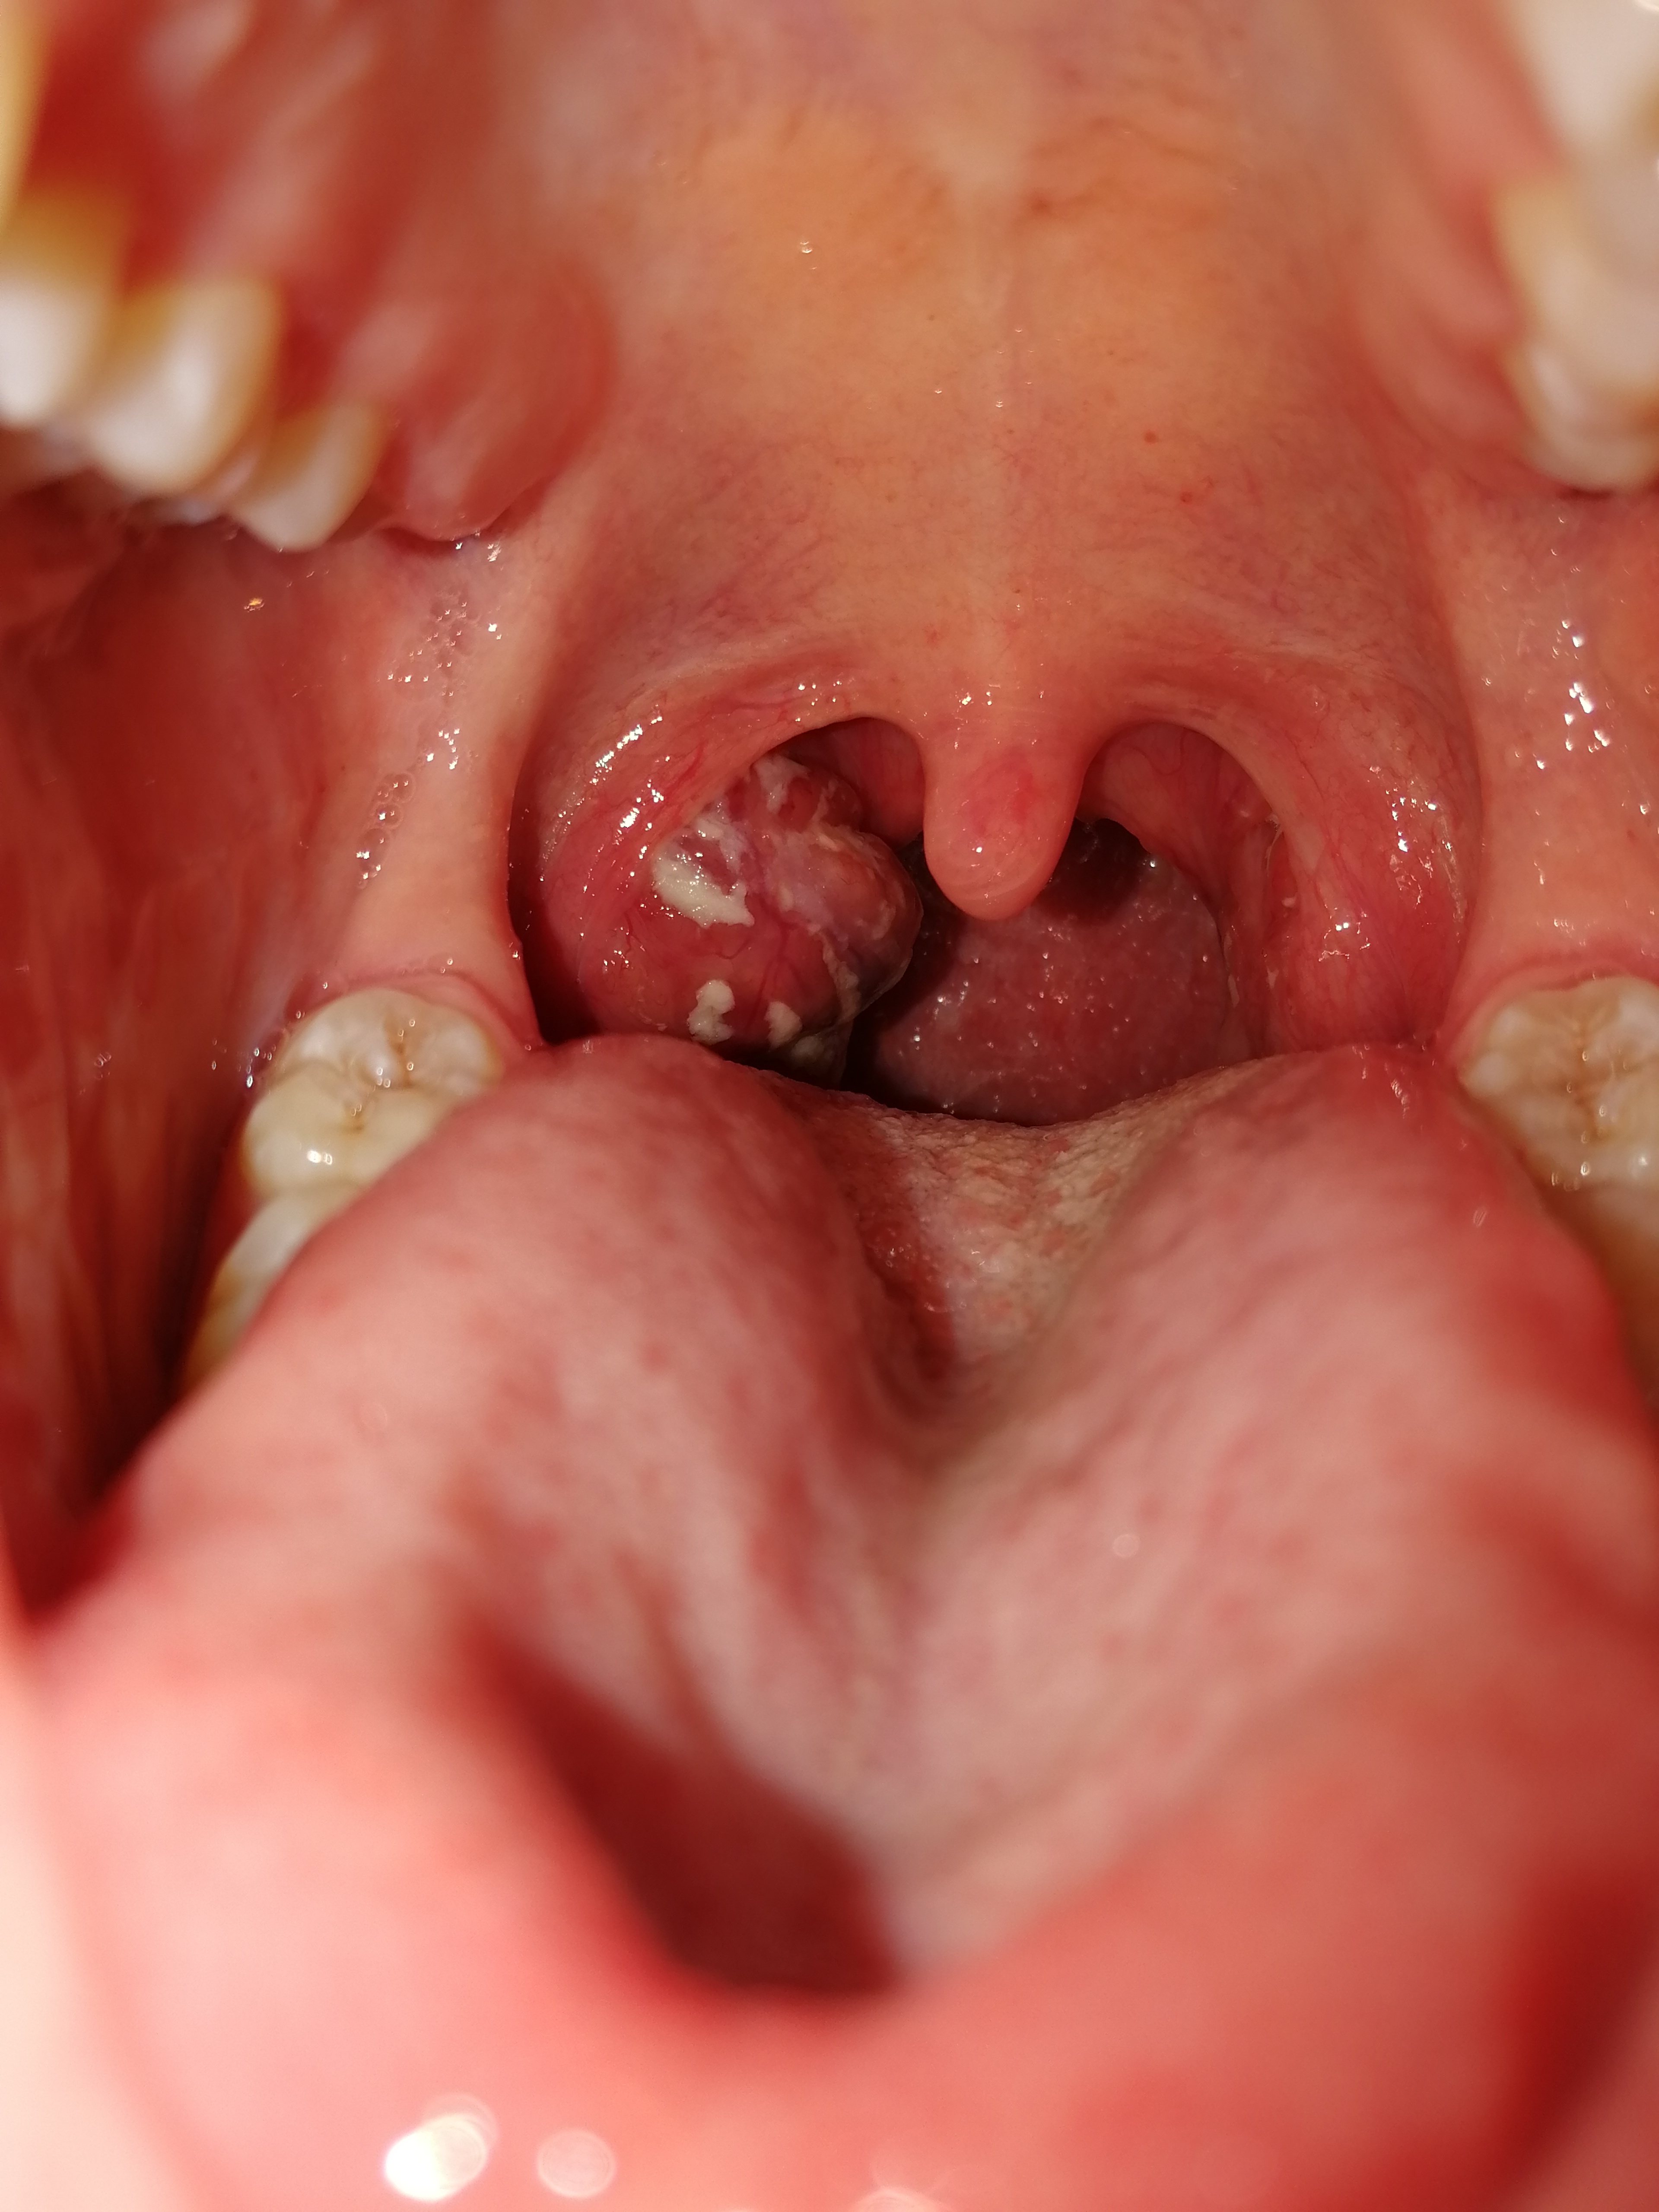

Dementsprechend stellen sich die Symptome lediglich einseitig dar Die Mandel ist gerötet und es bildet sich ein schmieriger, grauweißlicher und unangenehm riechender Belag Leiden Kinder an einer Tonsillitis können zusätzlich Beschwerden wie Bauchschmerzen und Erbrechen dazukommen. Die Mandel ist stark geschwollen und das Gaumenzäpfchen zur Gegenseite verdrängt Hier kann nur Ihr HNOArzt weiterhelfen Meist wird der Abszeß durch eine Punktion eröffnet und der Eiter abpunktiert Eine Gefahr besteht nun darin, dass die Erreger in die nahe gelegene Blutbahn eindringen (sogenannte Blutvergiftung) und sich so im ganzen. Weitere Hausmittel gegen geschwollene Mandeln Verrühren Sie ein Gemisch aus 1 Esslöffel Meerrettich (frisch gerieben) und 1 Esslöffel Honig in heißem Wasser und geben Sie noch einige Gewürznelken dazu.

Ja und die Mandel ist auch nicht eitrig oder so, sie ist einfach nur geschwollen und zerklüftet, es sind so komische Rillen drauf Ich hab einen Termin beim HNO in einer Woche Mal sehen, was er zu der Mandel sagt. Wer bei einem fieberhaften Infekt mit dem üblichen Drum & Dran über einen dicken Hals klagt, meint damit meist, dass dieser sich innen geschwollen anfühlt, vielleicht auch wehtut Schuld ist oft eine Mandelentzündung Die Mandeln sind kleine, den Lymphknoten ähnliche Gebilde, die tatsächlich mandelförmig aussehen. Sekret aus Mandel (einseitig), keine Entzündung Liebe Community, ich habe vor Monaten aufgrund eines Fremdkörpergefühls beim Schlucken (rechts) in meinen Hals geschaut und entdeckt, dass meine rechte Mandel größer ist als meine linke.

Ich habe vor ca 2 3 Jahren festgestellt, dass ich eine einseitige Schwellung der Mandel habe Vor einem Jahr war ich bei einem Hausartzt, dieser hat mich zu einem Klinikum geschickt Der dortige Arzt hat sich die Mandel angeschaut Er meinte damals, ob es sich um Krebs handelt könnte nur durch die Entfernung der Mandel festgestellt werden. Hi, Also ich hab vor zwei Wochen entdeckt dass meine mandel geschwollen ist, allerdings nur links Anfangs hatte ich auch Schmerzen Die sind zwar nun weg aber die Schwellung und die Schwellung des Lymphknoten links geht nicht zurück Beim HNO der auch einen abstrich gemacht hat kam nicht wirklich. Ein geschwollenes Gaumenzäpfchen (Uvula) ist erst mal kein Grund zur Sorge, es kann aber zu Schnarchen führen Oft treten die Schwellungen jedoch auch erst wegen dem Schnarchen auf.

Die Entfernung der Mandel stelle deshalb „eine der wirksamsten Maßnahmen dar, mit der die Gesundheit und damit das Lebensschicksal eines Menschen in günstiger Weise gesteuert werden kann“. Mögliche Vernarbungen mit der Muskulatur der Mandelbucht führen zur Unbeweglichkeit, die Mandel kann nicht mehr seitlich verschoben werden Wenn man mit einem Stäbchen auf die Mandeln drückt, tritt Eiter oder Detritus aus Der vordere Gaumenbogen ist gerötet, die Halslymphknoten sind geschwollen, schmerzen jedoch nicht. Dicke Mandeln was tun?.